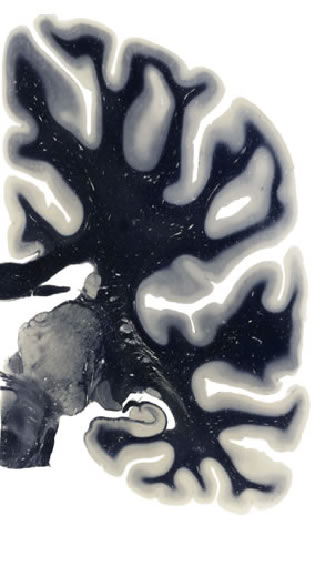

Frontal sections (Nissl) from the Atlas Brain: Gallery Slice Single

29,2 mm

Slice ID: r3-0303

Plate NR: 44

Position: 29,2 mm